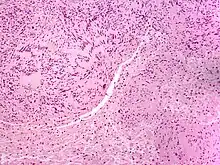

Solitary circumscribed neuroma

Neuromas can arise from different types of nervous tissue, including the nerve fibers and their myelin sheath, as in the case of genuine neoplasms (growths) like ganglioneuromas and neurinomas.